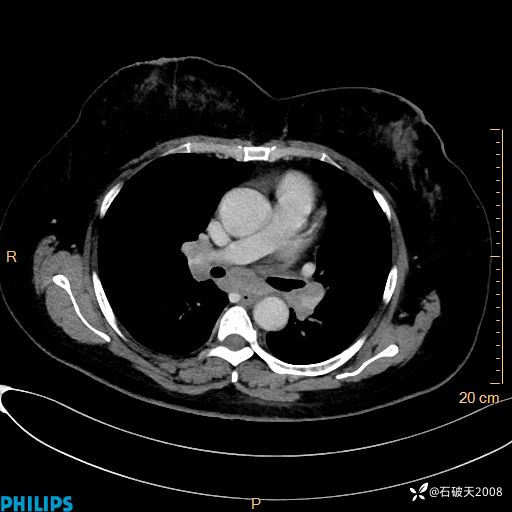

肺结节病?纵膈型肺癌?淋巴瘤?有点意思,欢迎围观

女 52岁 主 诉:咳嗽10余天,咳痰2天。

静脉期